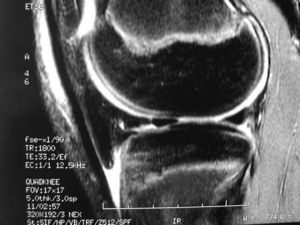

The knee is the largest synovial joint in the body and one of the most complex biomechanical systems known.1,2 This joint includes a condyloid joint between the condyles of the femur and the tibia and a saddle joint between the posterior surface of the patella and the patellar surface of the femur (Fig. 1). The upper tibiofibular joint, which is not involved in weight bearing, frequently communicates with the femorotibial joint.3